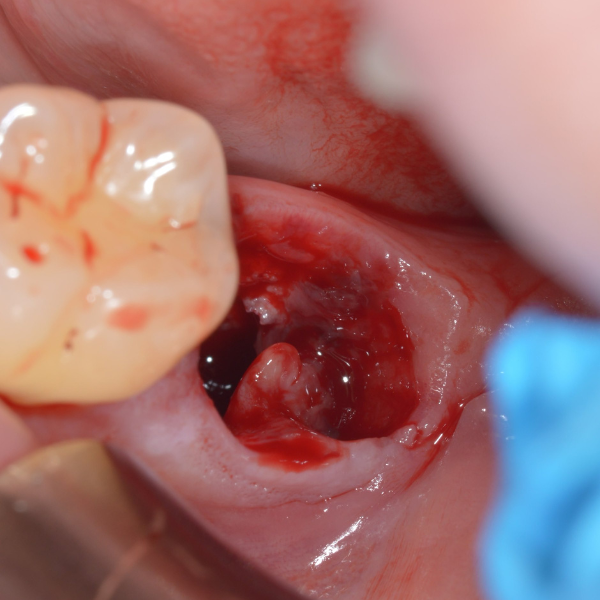

Tooth 14 slightly increased mobility, tenderness and bite pain. Suspected root fracture

Patient suffered from a root fracture. Needed removal and to restore hard and soft tissue.